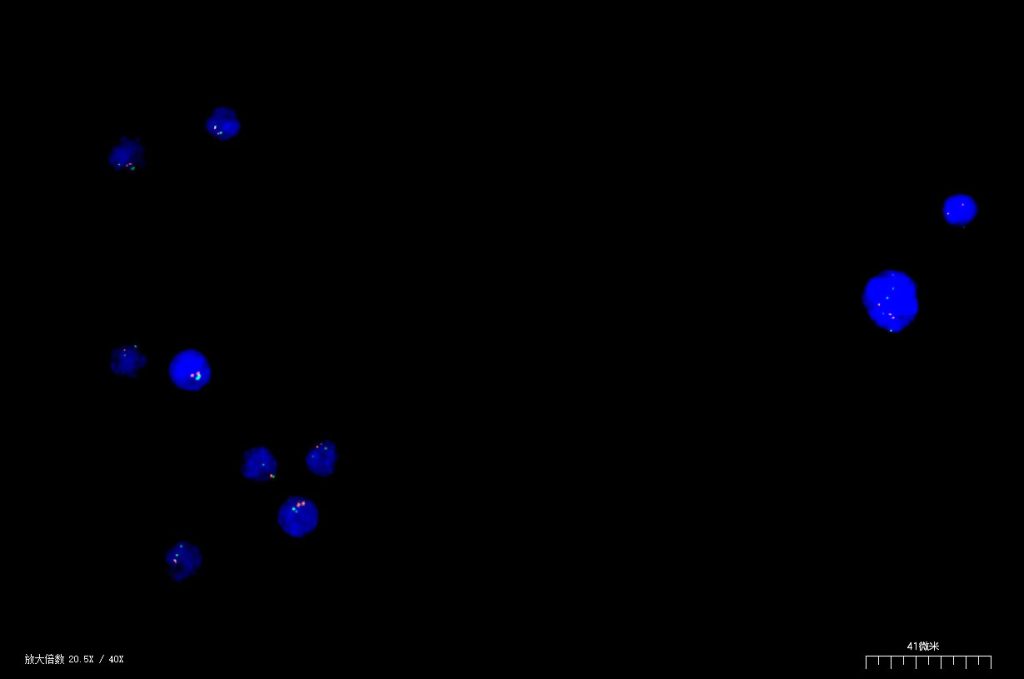

Fluorescence in situ hybridization (FISH)